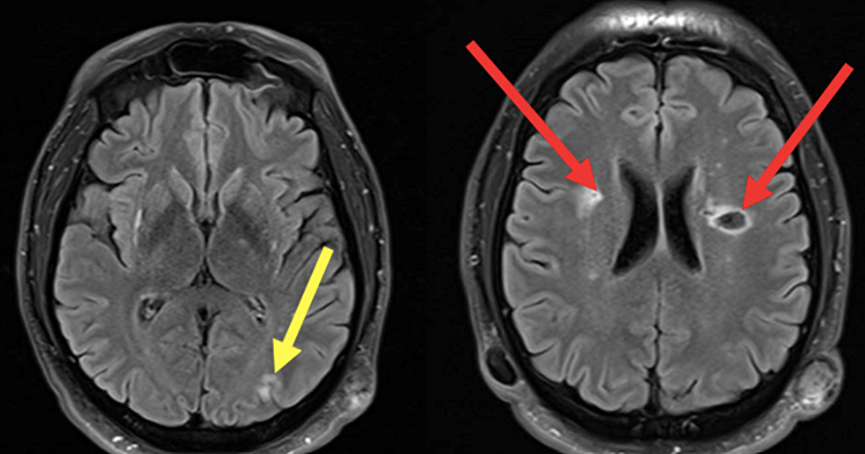

Le type d’hémianopsie est très important car il permet de localiser une atteinte neurologique, en connaissant le trajet des voies optiques.

Cette question supposait d’avoir bien en tête le schéma des voies optiques, et d’avoir des repères sur les principaux territoires vasculaires cérébraux et l’atteinte clinique associée. Il bien mentionné par le CEN que l’hémianopsie latérale homonyme gauche peut se voir dans un AVC sylvien superficiel droit.

Tableau d’après le Collège des enseignants de neurologie. Altération aiguë de la vision.